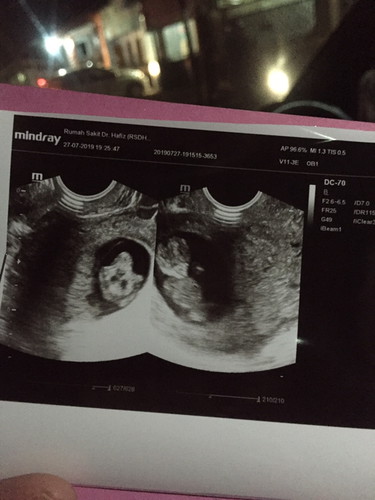

Janin kembar, satu di vonis cacat

Hancur hatiku, ini kehamilan kedua berusia 7minggu 2 hari. tadi sore USG transvaginal, dokter bilang kalau anak saya kembar (alhamdulillah saya mengucap syukur) Lalu kabar gak baik bilang kalau 1 janin tidak normal ? Satu janin lagi normal.. Doain saya kuat bunda2, atau bunda punya pengalaman seperti saya?